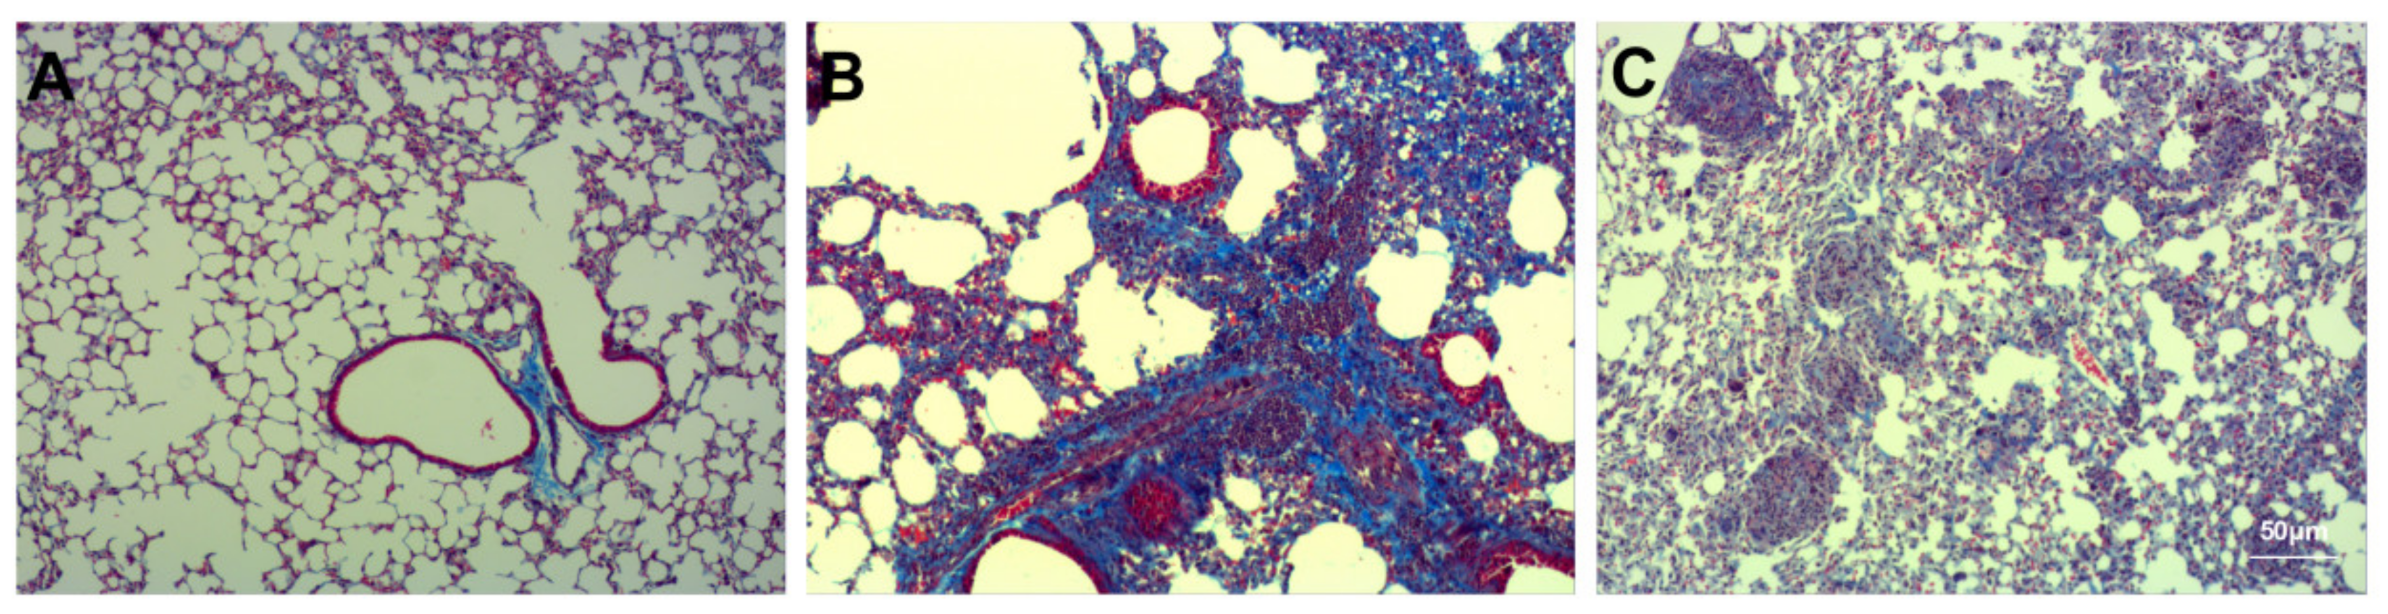

3.3. Assessment of Pulmonary Fibrosis